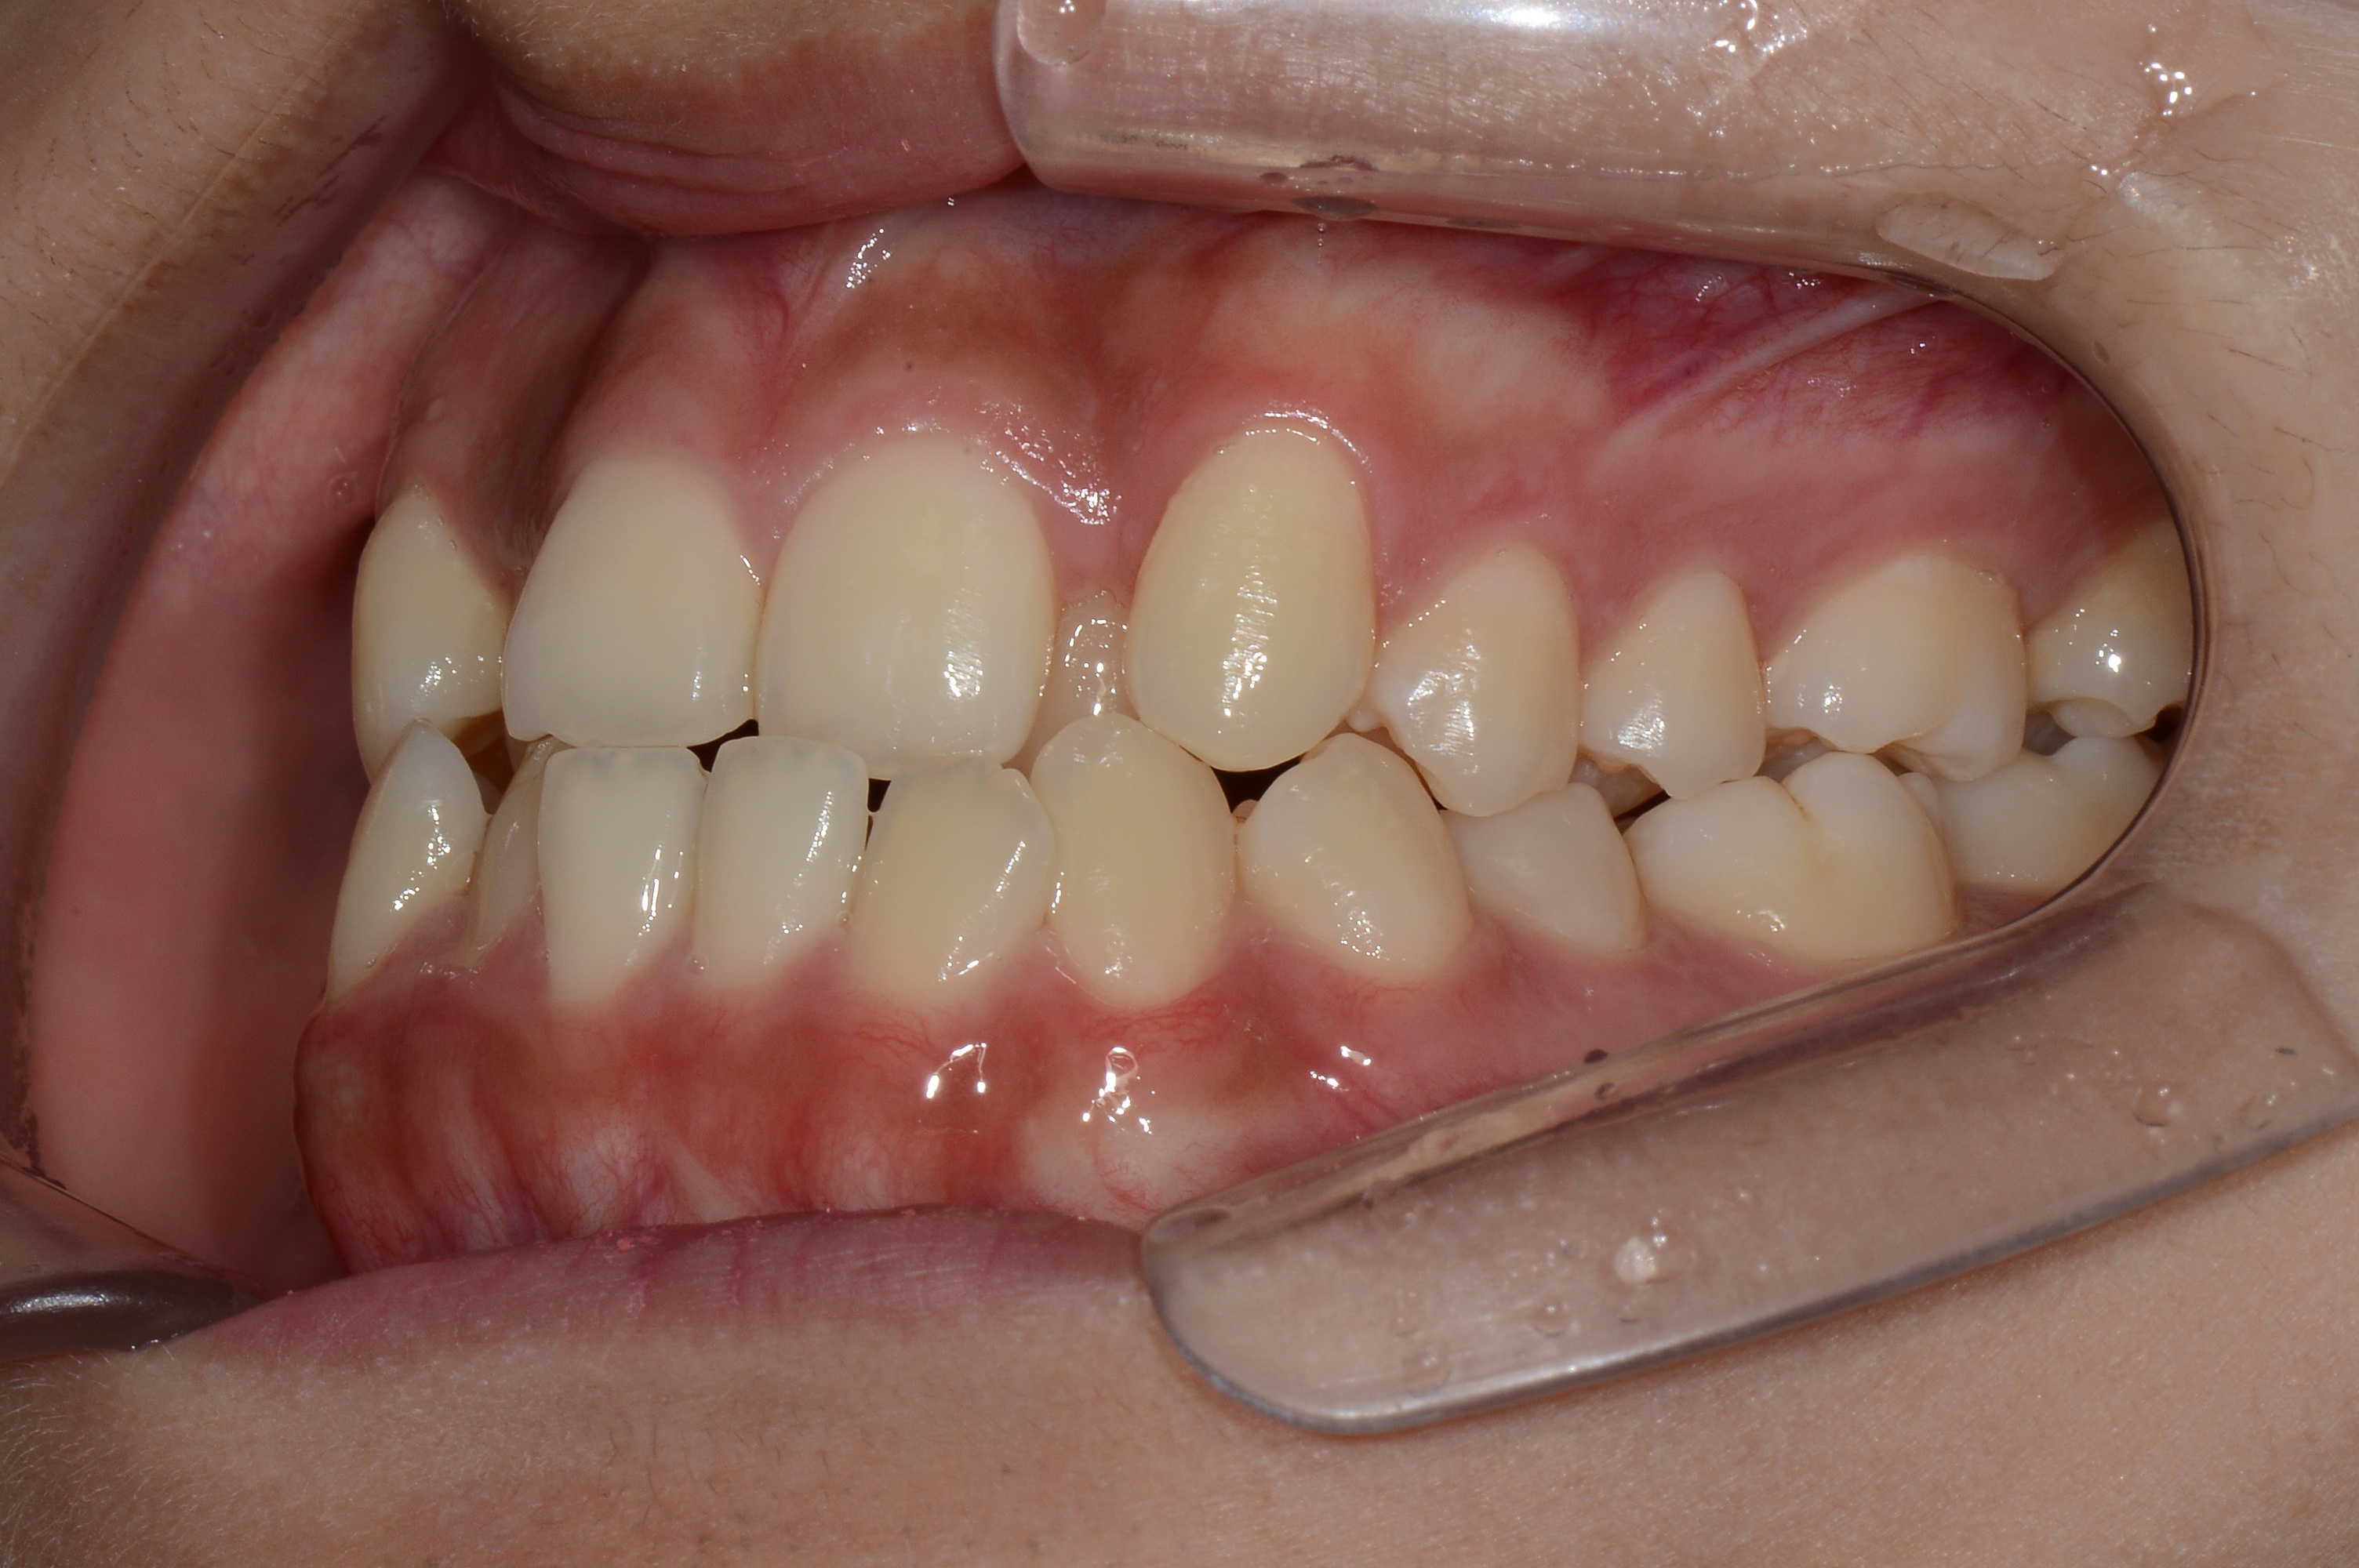

치료 후 사진입니다.